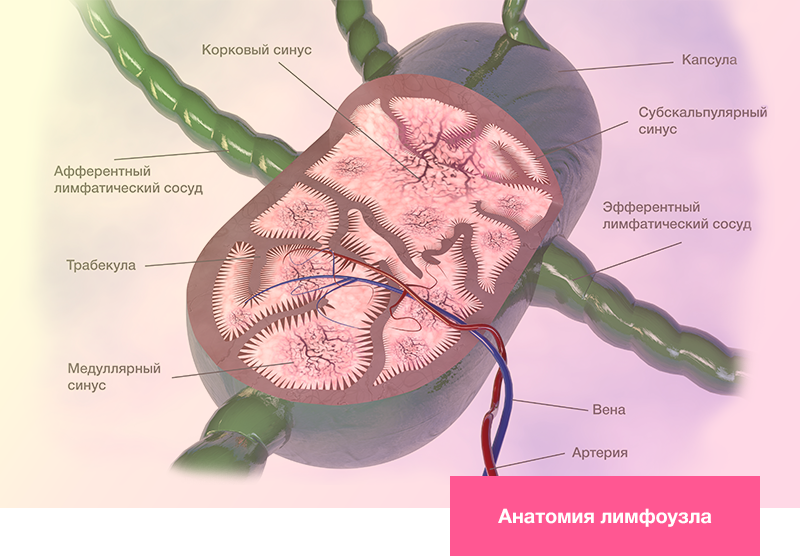

Изображения и схемы: как выглядит лимфа